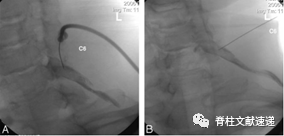

入路1:C臂透视下前外侧入路

体位:此病例行左侧椎间孔阻滞治疗,取颈部过伸头向右侧倾斜30°(图A所示),为了防止病人在穿刺过程中改变体位,在额头部位用胶带固定头部保持体位(图B所示)。并通过一个血管钳在体表,透视下标记穿刺路径和穿刺点(图C所示)

穿刺针位置:穿刺针的点位于目标节段神经根孔在体表投影的下外侧,并用记号笔在体表作标记.

穿刺过程:选择25#带尖的穿刺针,大多数情况下方向为从尾端向头端,外展45°,并在穿刺过程中患者自述出现根性疼痛,小心回抽穿刺针,并回退几毫米,旋转针尖口方向再次穿刺,直到触及骨性结构,然后注射1-2ml碘海醇造影剂,通过造影剂分布情况(造影剂在神经根周围弥散性分布为最佳分布图像),确定穿刺针尖位于椎间孔的下外侧,并排除误入血管(正常情况下无血管填充,若进入血管则会出现血管流动影及造影剂吸收)及脊髓风险。

如果在造影过程中无弥散性分布,需重新调整位置;并重复以上操作以获得最佳穿刺位置。

在穿刺过程中询问患者有无不适,若没有,作者采用2%利多卡因和醋酸倍他米松注射液1.5ml,量维持在1.0-1.6ml之间,注意最大量不要超过1.6ml,穿刺完毕后拔出针头,局部稍加压按压30-60秒。